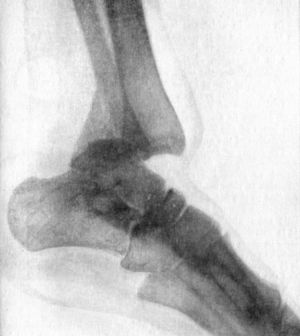

93.Section through Ankle-joint showing relation of Epiphyses to Synovial Cavity186

94.Radiogram of Pott's Fracture, with Lateral Displacement of Foot187

95.Ambulant Splint of Plaster of Paris189